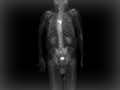

During a bone scan, a radioactive substance called a tracer is injected into a vein in your arm. The tracer travels through your bloodstream and into your bones. Then a special camera takes pictures of the tracer in your bones.

Areas that absorb little or no amount of tracer appear as dark or "cold" spots. This could show a lack of blood supply to the bone or certain types of cancer.

Areas of fast bone growth or repair absorb more tracer and show up as bright or "hot" spots in the pictures. Hot spots may point to problems such as arthritis, a tumor, a fracture, or an infection.

You will lie on a table, with a large scanning camera above you. It may move slowly above, below, and around your body, scanning for radiation released by the tracer and producing pictures. The camera does not produce any radiation.

Bone scan

Normal:

The radioactive tracer is evenly spread among the bones. No areas of too much or too little tracer are seen.

Abnormal:

The tracer has accumulated in certain areas of the bone, indicating one or more "hot" spots. Hot spots may be caused by a fracture that is healing, bone cancer, a bone infection (osteomyelitis), arthritis, or a disease of abnormal bone metabolism (such as Paget's disease).

Certain areas of the bone lack the presence of tracer, indicating one or more "cold" spots. Cold spots may be caused by a certain type of cancer (such as multiple myeloma) or lack of blood supply to the bone (bone infarction).